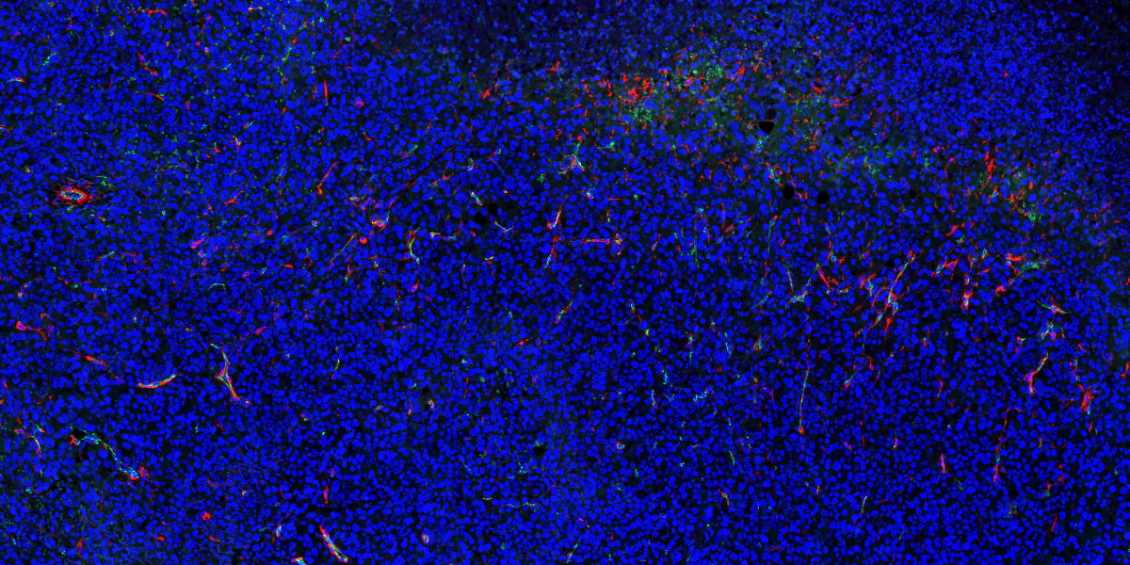

陕西石蜡切片免疫荧光不可避免会产生自发荧光。

1.取材的时候灌注取材,把红细胞冲洗干净;

2.脱蜡必须彻底,封闭、洗涤等过程也需充分;

3.抗体在使用前最好先离心处理并尽量从上方吸取,抗体的浓度过高也会产生自发荧光,所以可以预实验摸清最合适的抗体浓度再进行正式实验;

4.如若自发荧光很强,严重影响染色效果,亦可采用自发荧光去除剂进行去除。